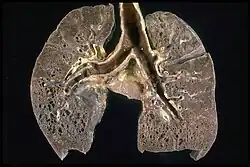

-

Hilar adenopathy especially on the person's left (AP CXR) -

Hilar adenopathy especially on the person's left (lateral CXR) -

Hilar adenopathy especially on the person's left (coronal CT) -

Hilar adenopathy especially on the person's left (transverse CT)